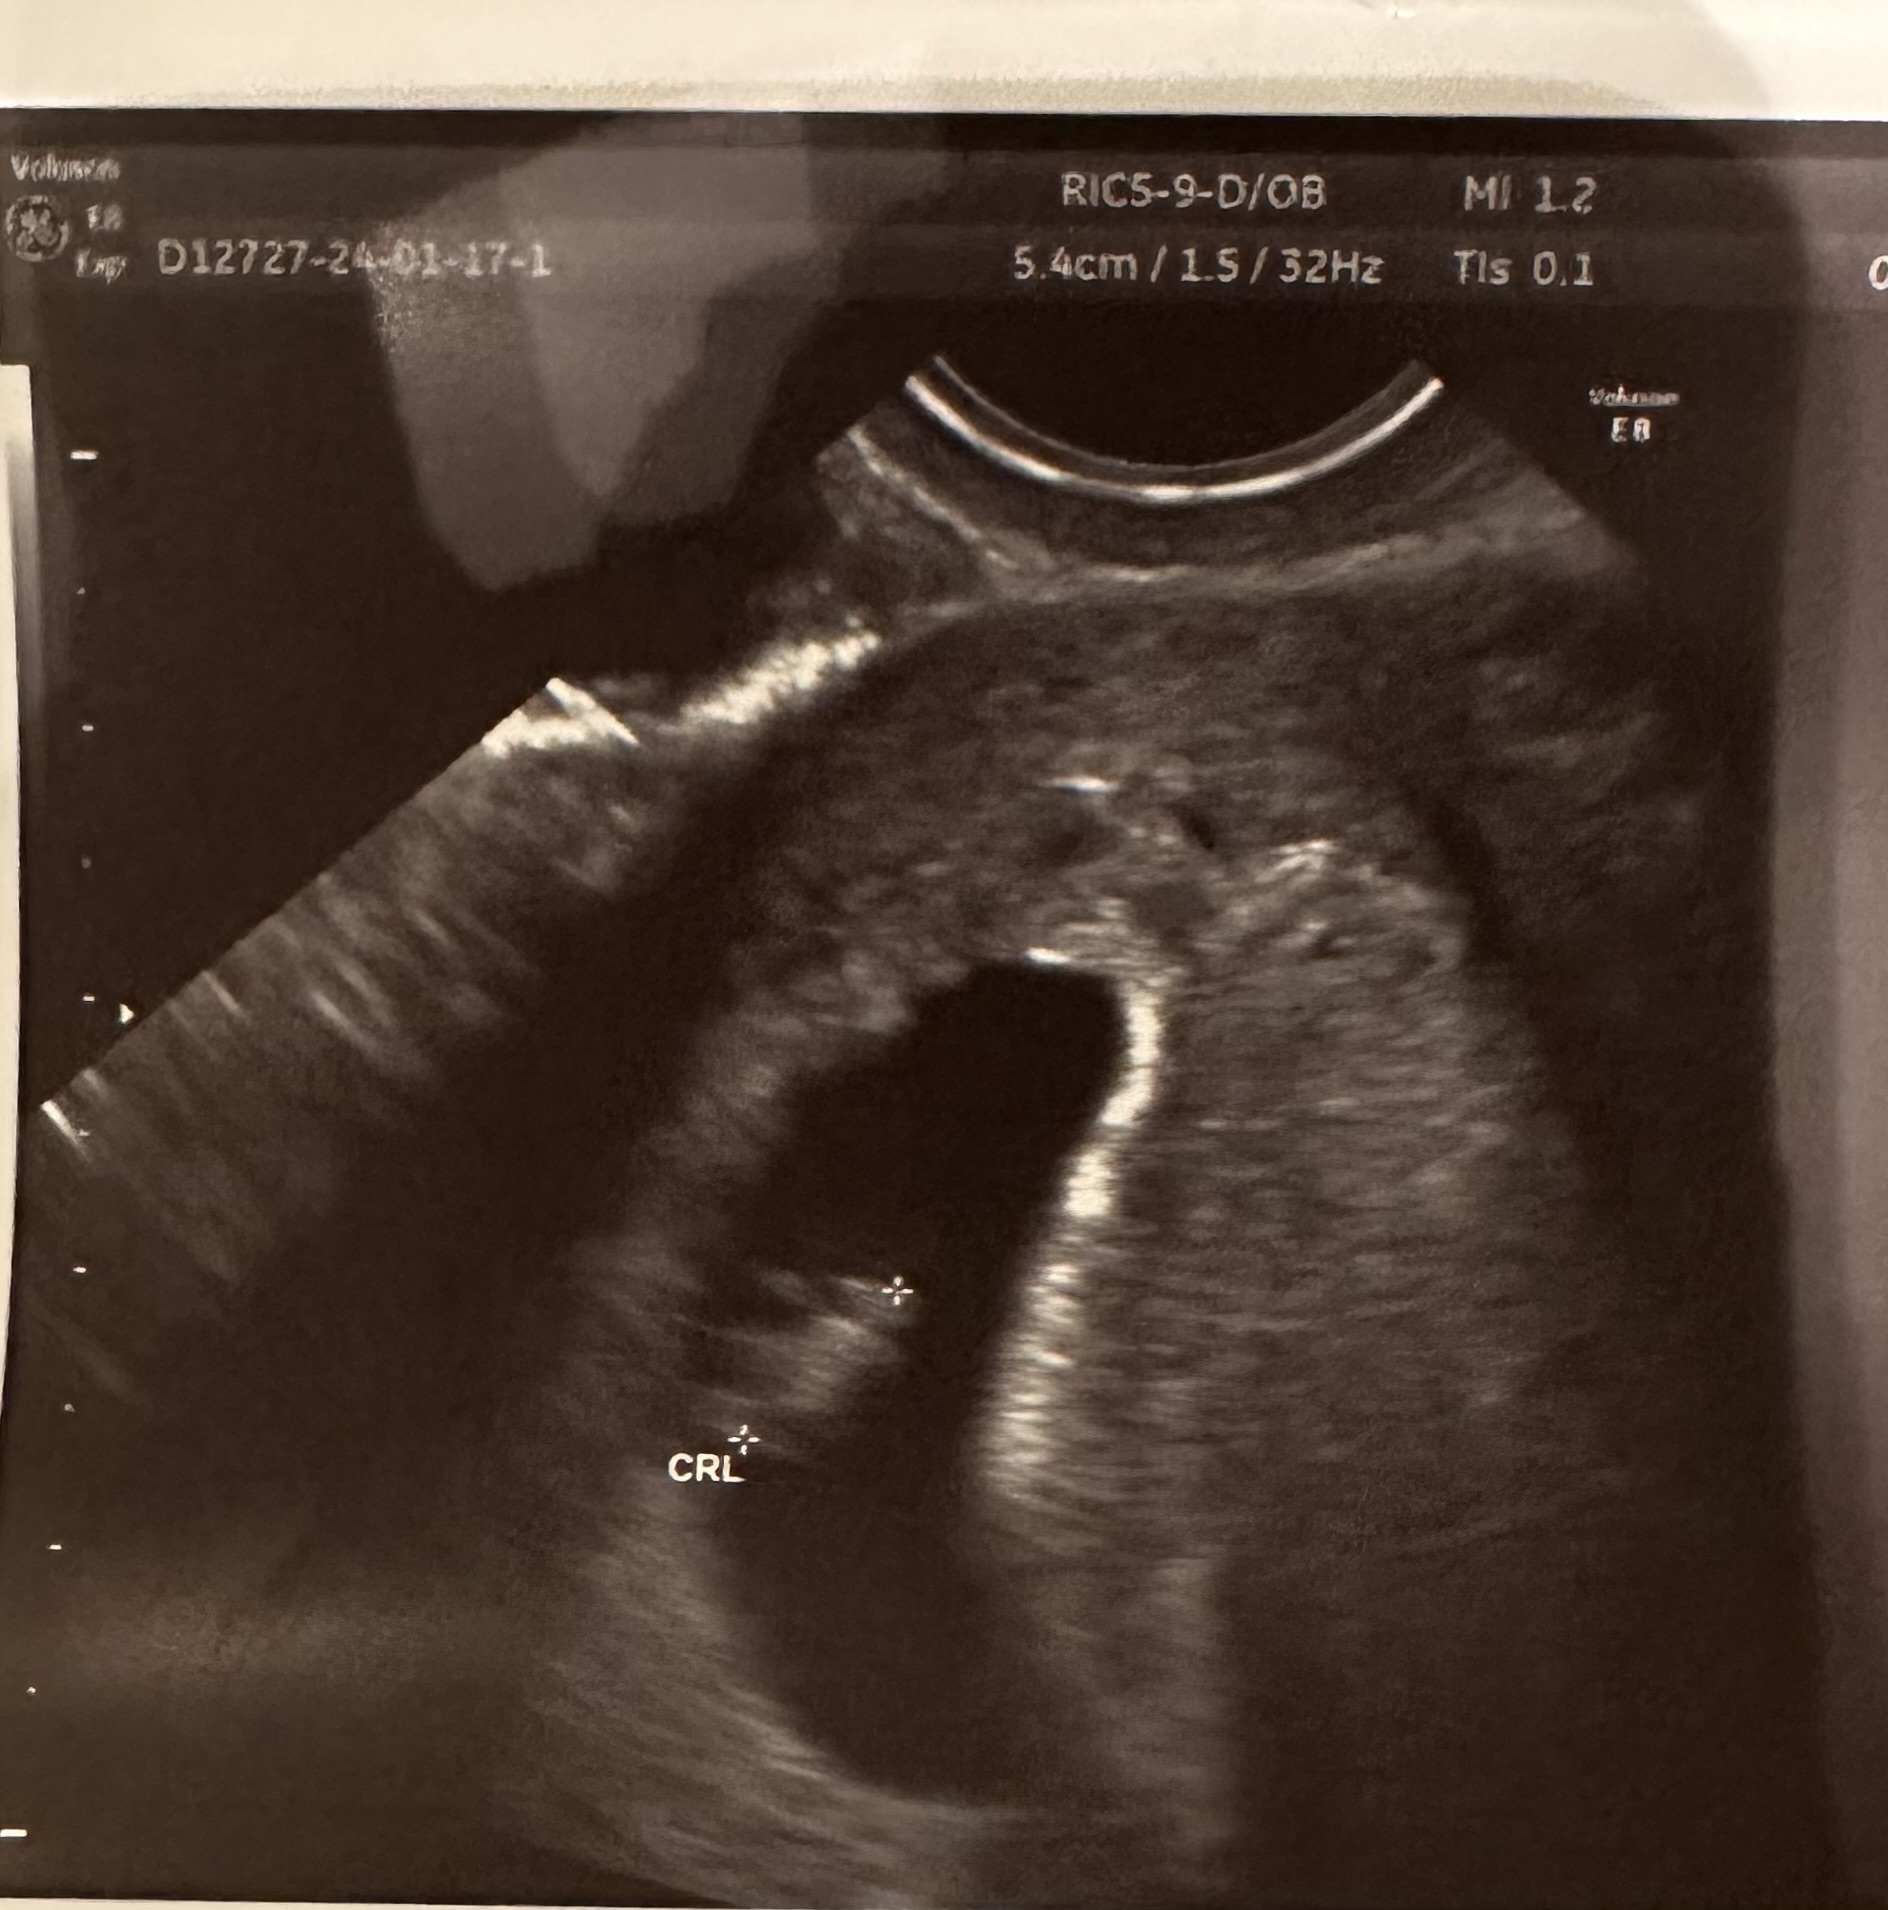

Mamy małego człowieka, 8,5mm!Tym razem było widać już elegancko jak bije serduszko, a nie jakaś migająca dioda

A tutaj ciocie przedstawiam fasolkę![]()

CudownieMamy małego człowieka, 8,5mm!Tym razem było widać już elegancko jak bije serduszko, a nie jakaś migająca dioda